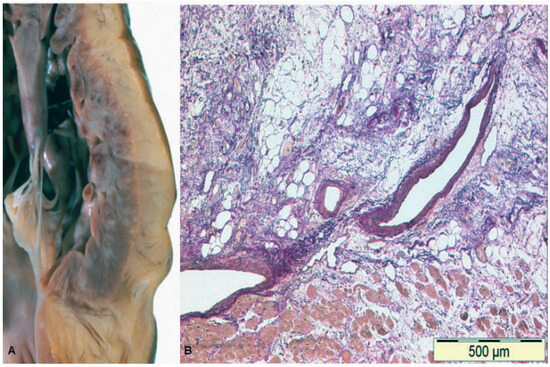

Case report. A 63-year-old hypertensive male presented with atypical chest discomfort and breathlessness on exertion [...]